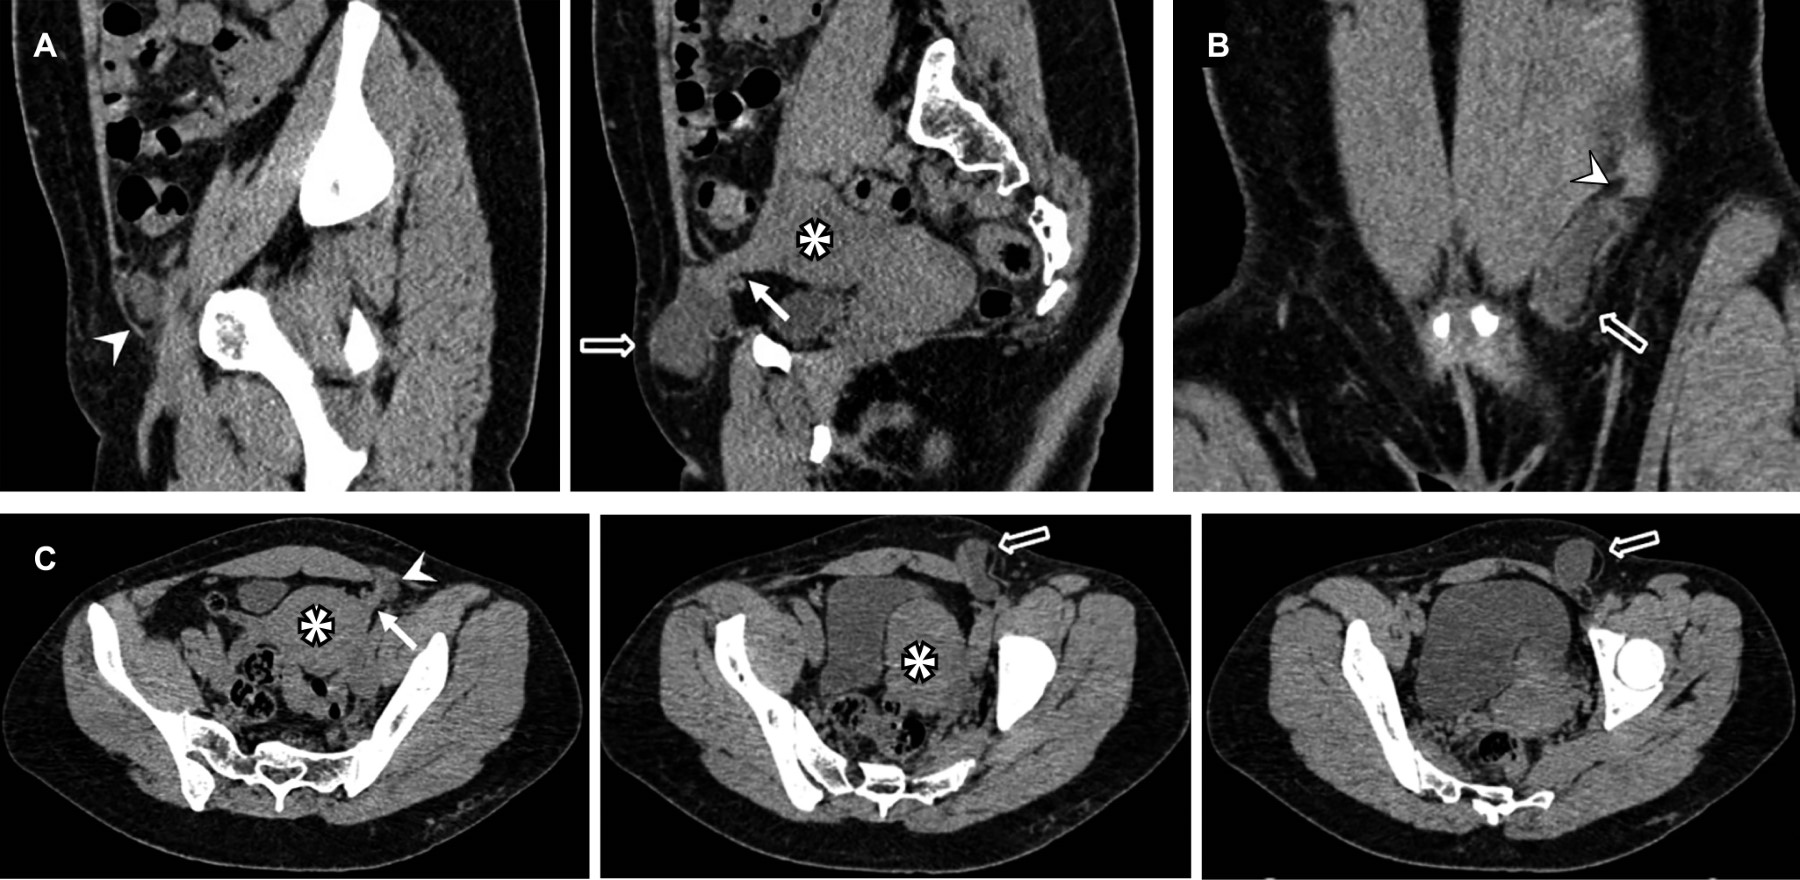

Figure 1